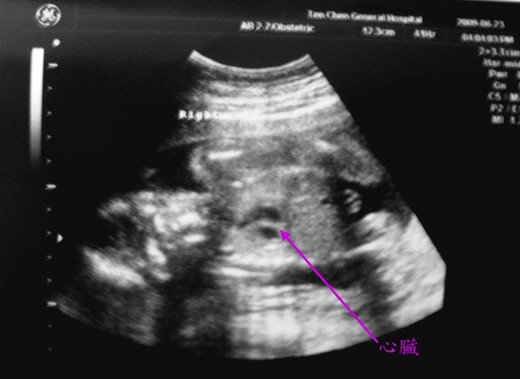

第二次:過了1小時又遇到幫我產檢的醫師,就跟她說了剛才的事情

他就讓我自己去用產科專用的超音波機~

看到心跳就安心了